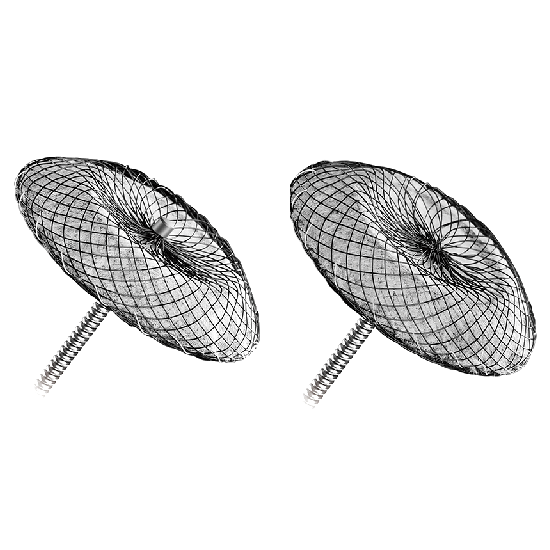

Lepu yüksek teknoloji tıbbi cihazlar ve ekipmanları

Kardiyovasküler tıbbi cihazlarda lider lepu medical, 190 iştiraki küresel bir ağa sahiptir. 214 ce sertifikalı ve 34 fda onaylı ürünle lepu, tıbbi cihazları, ilaçları, sağlık hizmetlerini ve kalp bakımı için mobil sağlık hizmetlerini kapsayan entegre bir platform kuruyor. Şirket sırasıyla 2009 ve 2022 yılında shenzhen borsası (300003) ve İsviçre borsasında listelenmiştir.